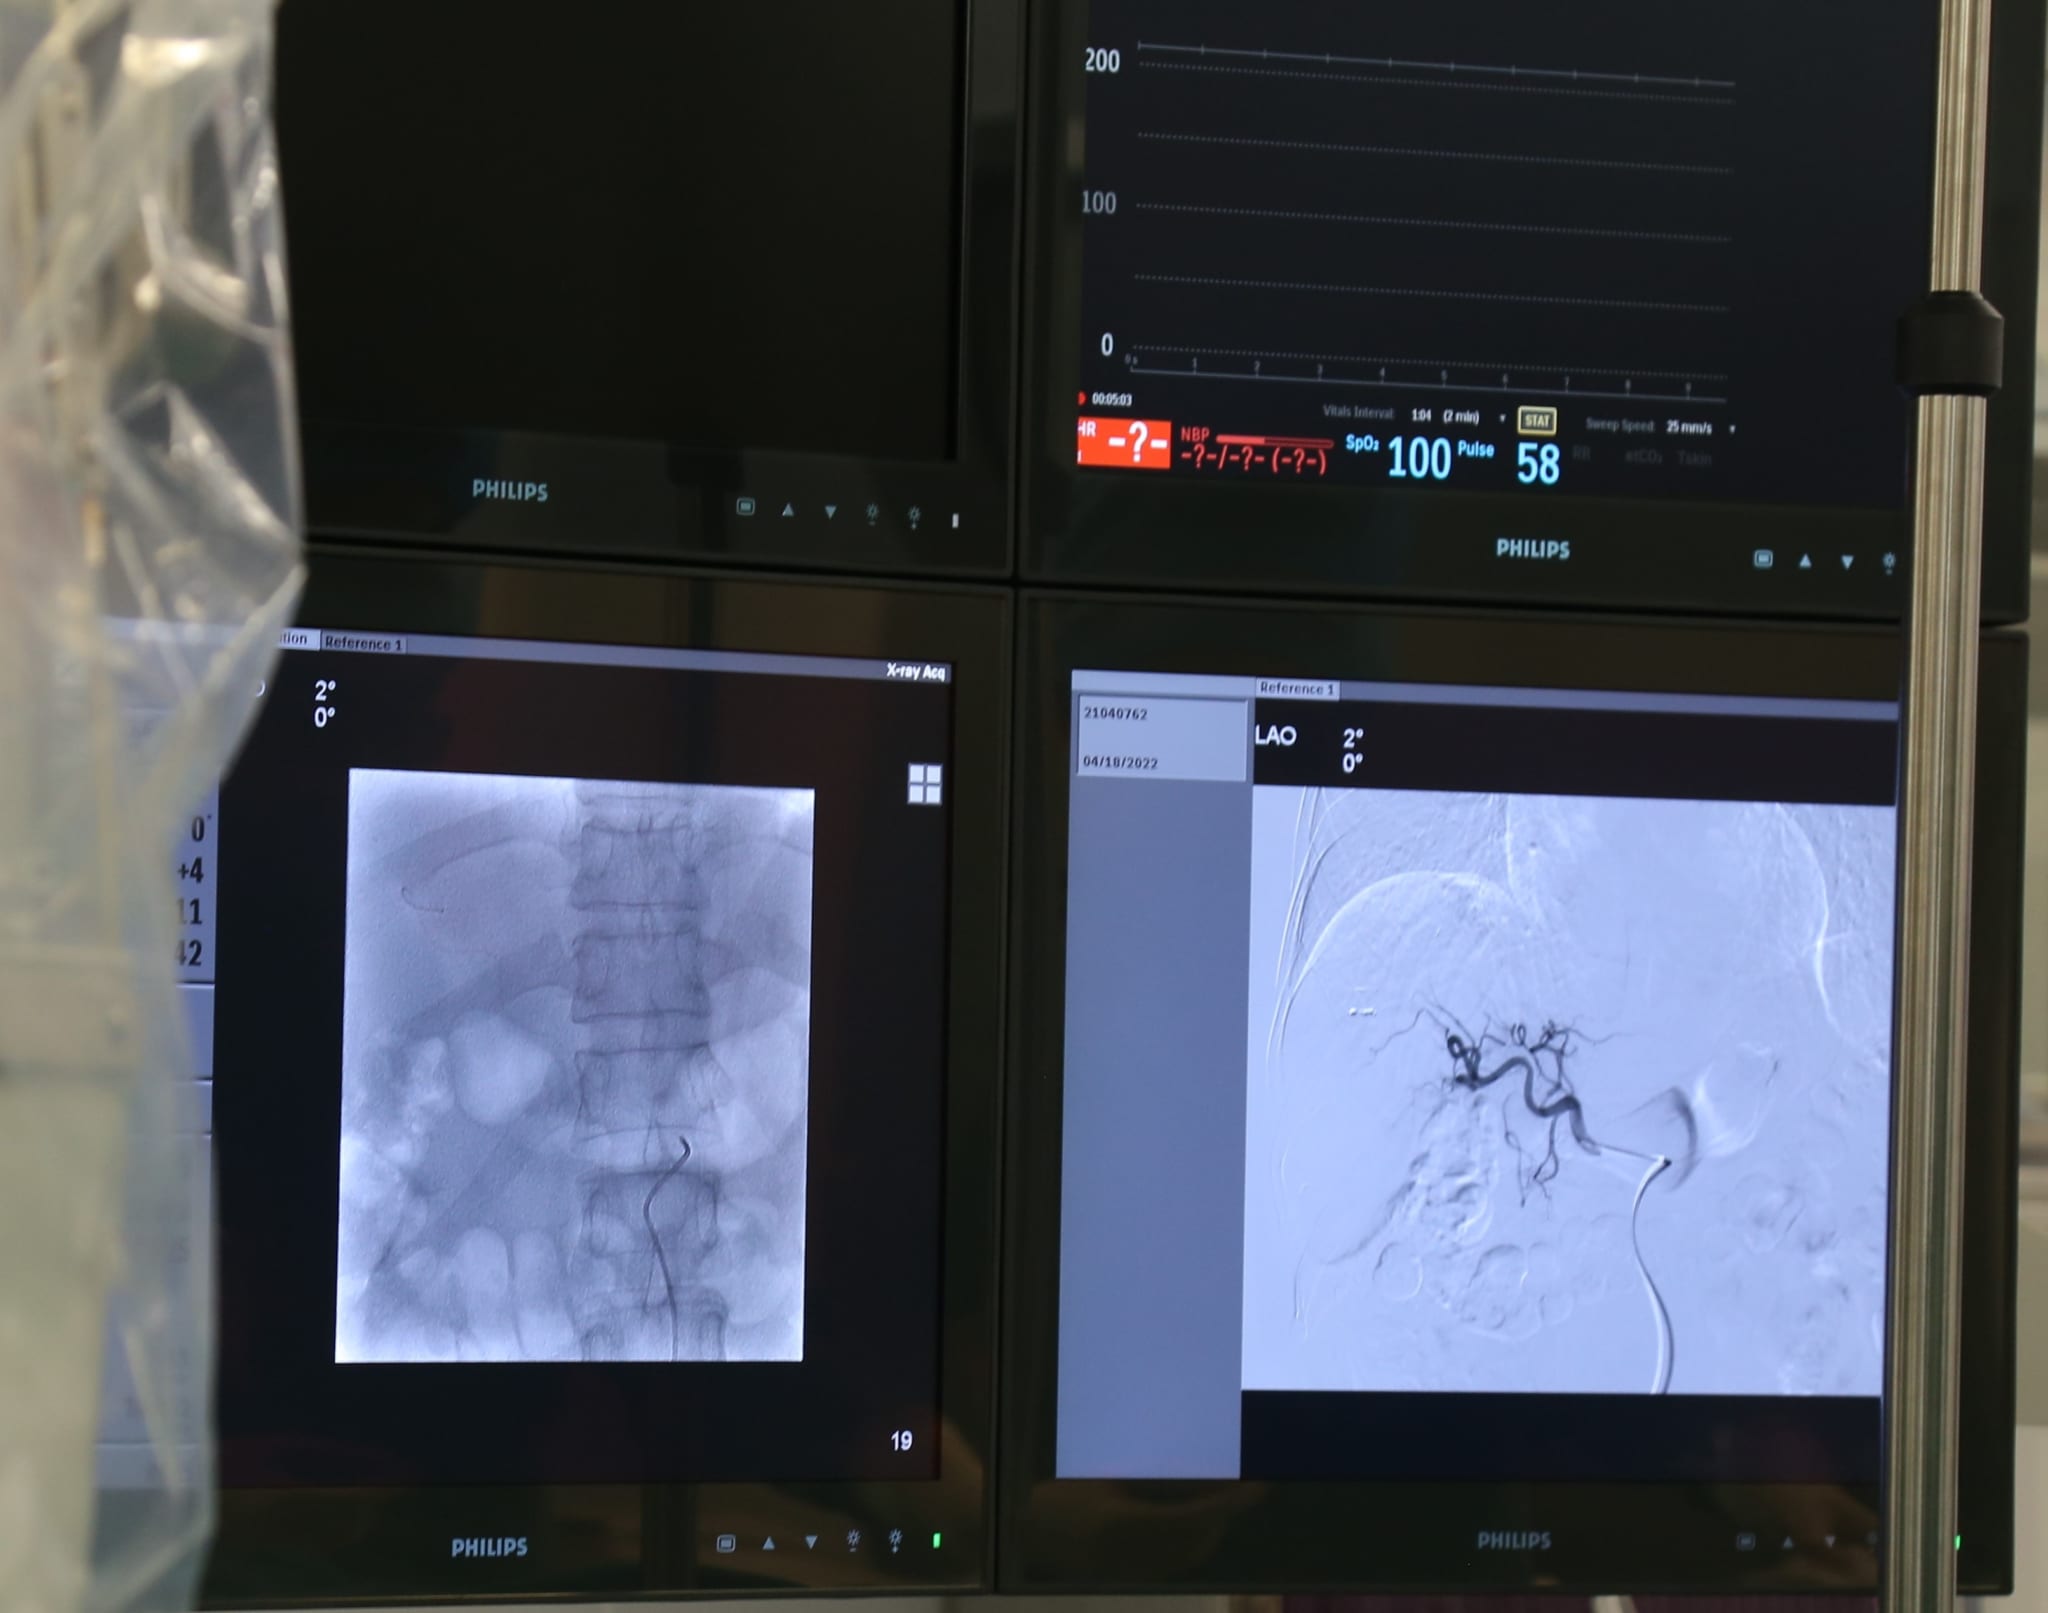

Thực hiện thành công phương pháp Nút động mạch điều trị ung thư gan dưới hướng dẫn của hệ thống máy số hoá xoá nền (DSA)

Nút mạch khối u được coi là biện pháp hiệu quả nhất đối với những trường hợp như bệnh nhân trên. Nhờ sự hỗ trợ từ hệ thống máy số hoá xoá nền (DSA), bác sĩ Bệnh viện Đa khoa Quốc tế Hải Phòng có thể đưa các vi ống thông chính xác tới nhánh mạch máu nuôi khối u (siêu chọn lọc) sau đó tiến hành bơm thuốc diệt u theo các nhánh này, giúp cho tập trung nồng độ thuốc tại khối u, hạn chế tác dụng phụ toàn thân (rụng tóc, đau…) như khi dùng phương pháp hoá trị toàn thân. Đây là phương pháp điều trị mới, thủ thuật an toàn, can thiệp tối thiểu, không cần phải phẫu thuật. Bệnh nhân chỉ cần giảm đau và gây tê tại chỗ, không cần thực hiện gây mê, vẫn tỉnh táo trong quá trình thực hiện. Phương pháp nút mạch khối u được chứng minh là cải thiện chất lượng cuộc sống và thời gian sống với bệnh nhân ung thư gan, đặc biệt có thể lập lại phương pháp này nhiều lần để điều trị.

Nút mạch trên hệ thống chụp mạch số hóa xóa nền DSA là kỹ thuật cao. Việc triển khai thành công kỹ thuật này đã đem đến hy vọng mới cho những bệnh nhân mắc bệnh ung thư gan đồng thời khẳng định vị thế, tay nghề chuyên môn của đội ngũ y, bác sĩ tại Bệnh viện Đa khoa Quốc tế Hải Phòng. Từ đó, không ngừng nâng cao chất lượng khám, chữa bệnh cho người dân ngay tại Hải Phòng và các vùng lân cận.